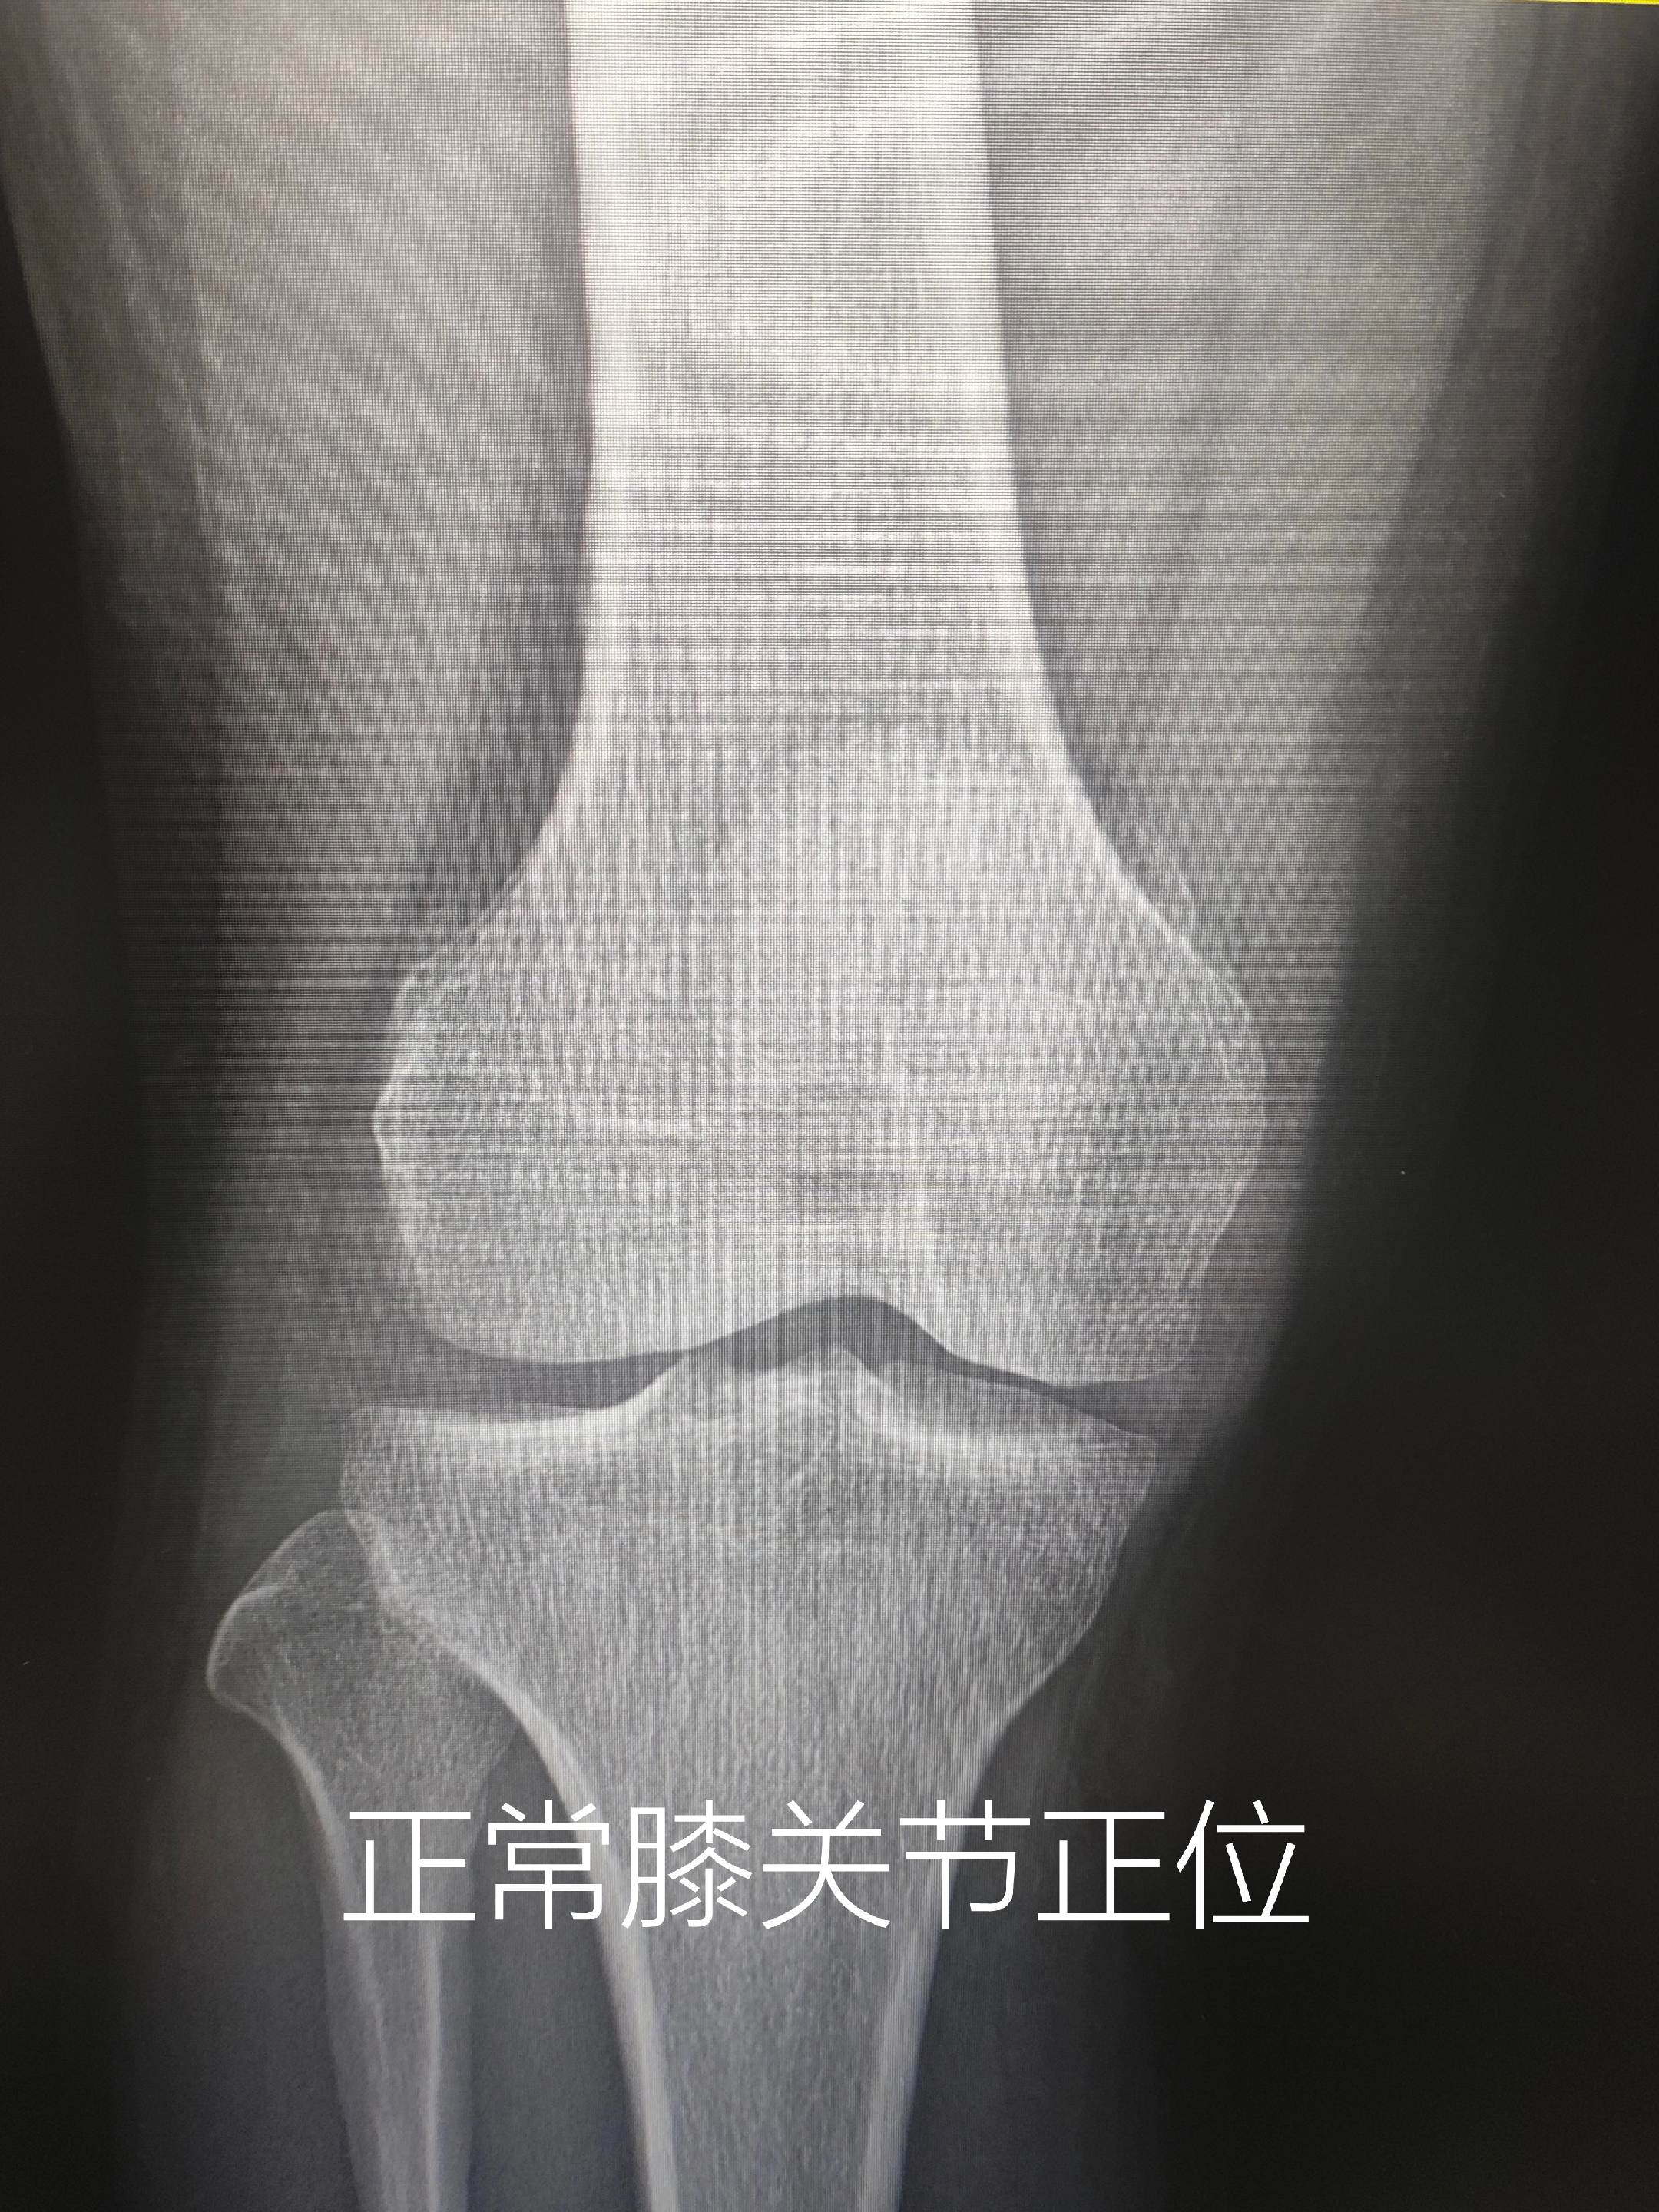

膝关节痛。